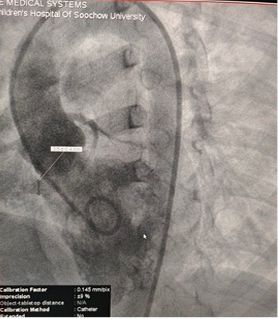

Case Sharing | Successful Closure of Multi-Exit Membranous Septal Aneurysm-Type VSD Using MemoSorb Biodegradable Occluder

Успешное закрытие многоэкранного мембранного септальная аневризма типа VSD с использованием полностью биоразлагаемого окклюдера MemoSorb

Диаметр основания: ~ 6,1 мм с несколькими точками выхода

Мембранно-подобная ткань, наблюдаемая над дефектом

Цветовой допплер: шунтирующий поток слева направо

Диагноз: Перимембранозный ВСД

Задача: Множественные выходы хрупкой мембранной ткани

Selected MemoSorb ABFDQ-II 9 occluder based on intraoperative angiography and echocardiographic assessment.